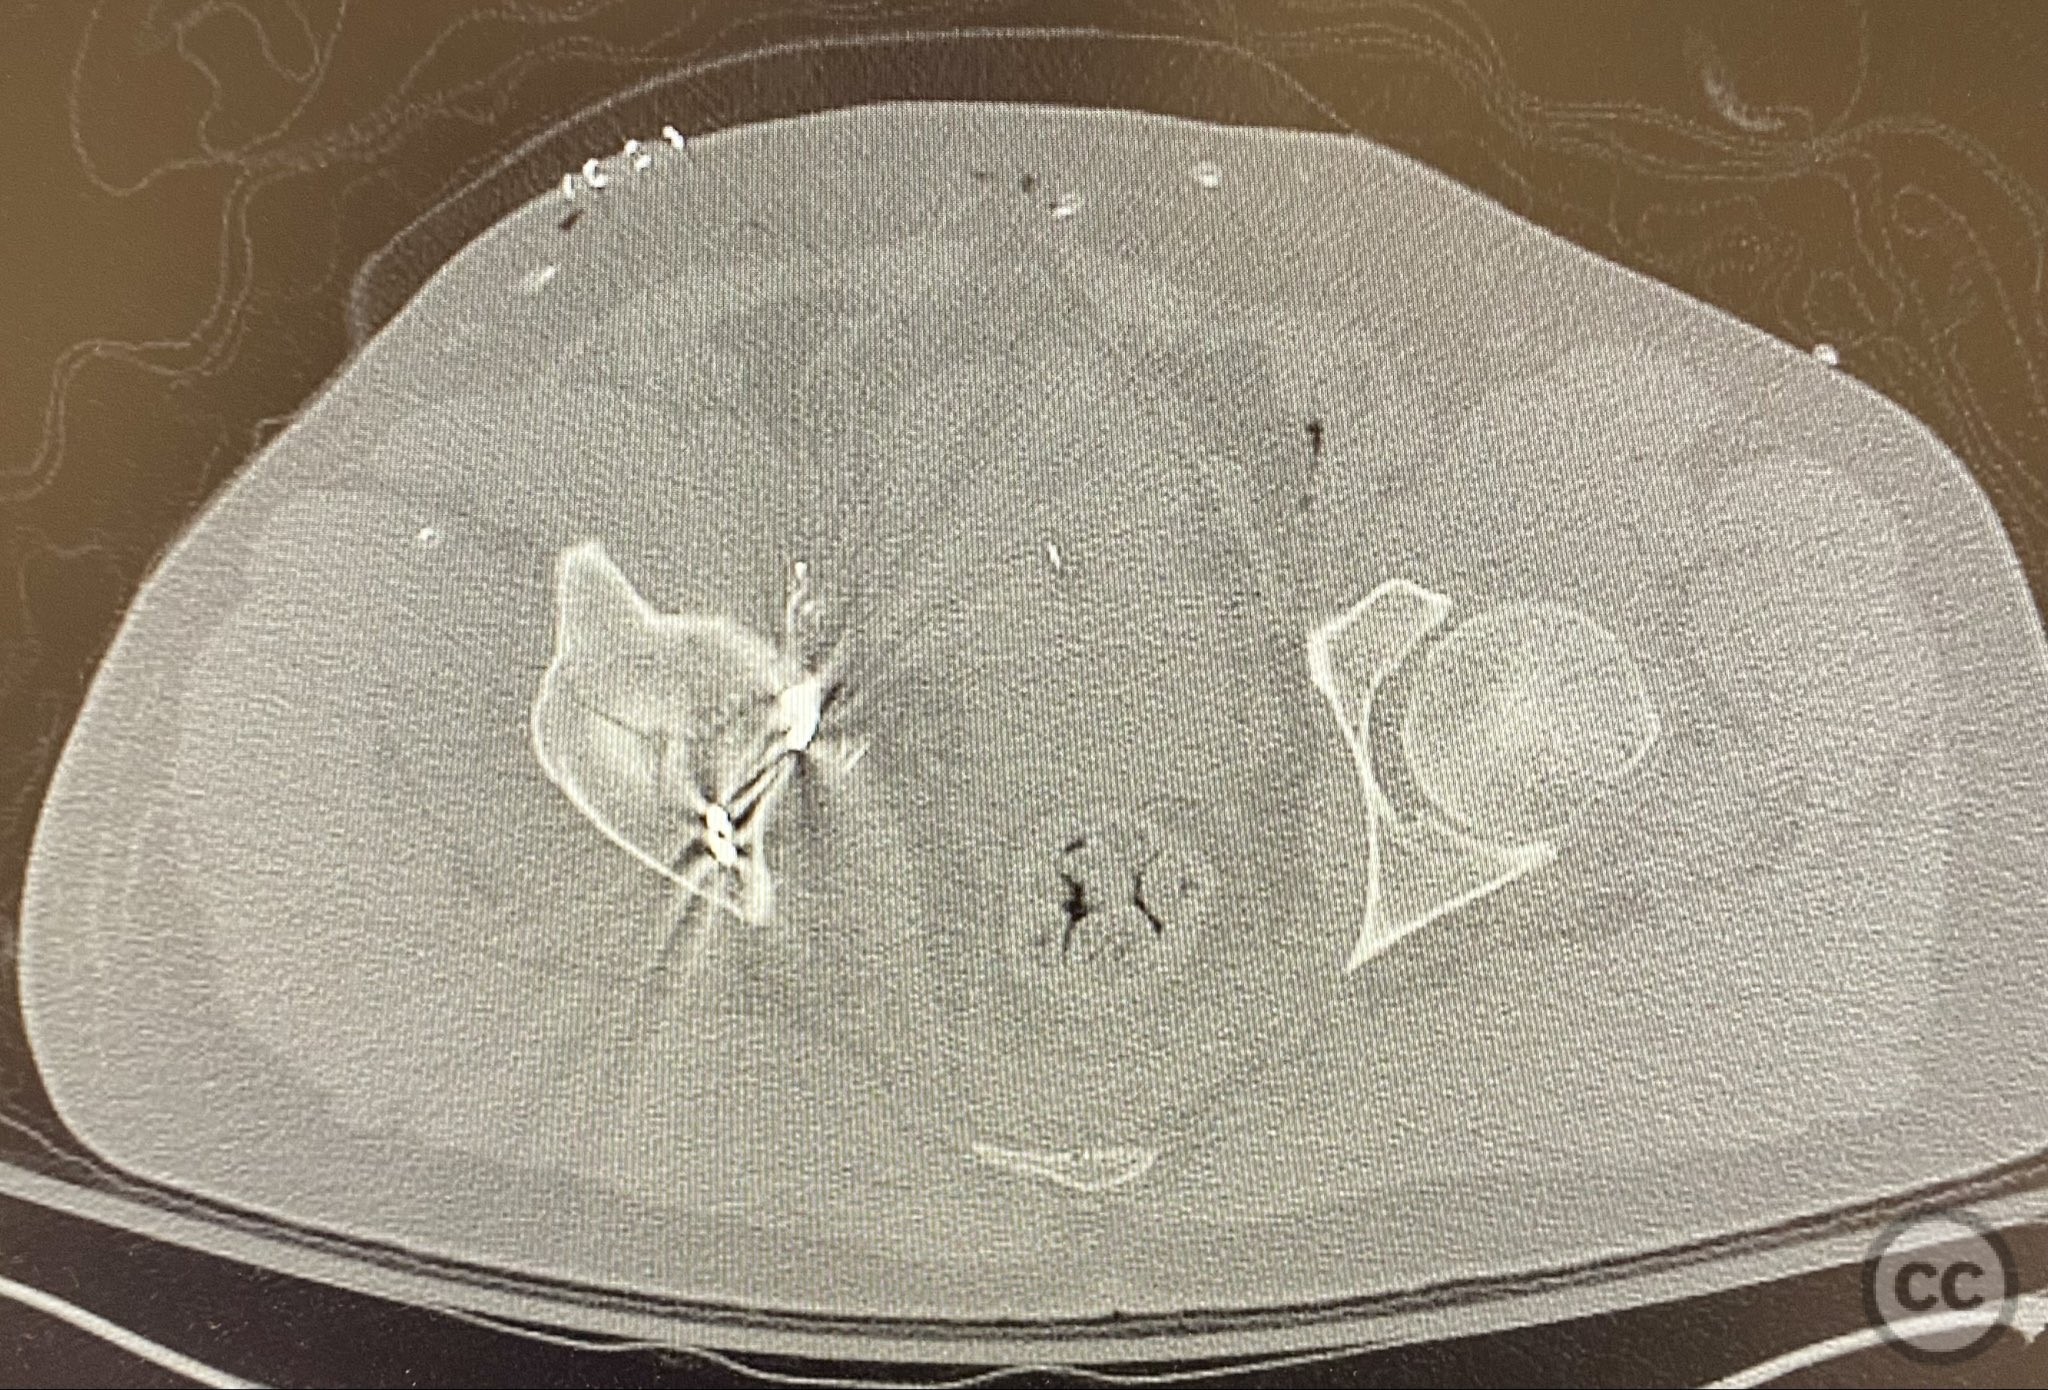

Clinical and radiological findings:  A patient presented with a combined anterior column and posterior hemi-transverse (AC/PHTr) acetabular fracture. Plain radiographs demonstrated multiple displaced fragments involving the acetabular dome and femoral head region, with clear disruption of the anterior column and posterior transverse components. Advanced imaging, including axial and coronal CT, provided detailed visualization of cortical surface displacement, fragment orientation, and associated soft tissue status. The edge of the intact dome and femoral head injuries were identified, as well as a residual defect at the edge of the dome following reduction. AO/OTA classification: 62B2 (anterior column with posterior hemitransverse).

Surface renderings from preoperative imaging facilitated intraoperative correlation between radiographic and fluoroscopic views, aiding in precise interpretation of fragment orientation during reduction. The use of focal plates allowed for maintenance of provisional reductions with bone holding clamps during definitive fixation. Restoration of radiographic lines was confirmed on intraoperative AP fluoroscopy, while postoperative axial CT demonstrated successful central dome repair with a residual edge crush defect at the dome margin.